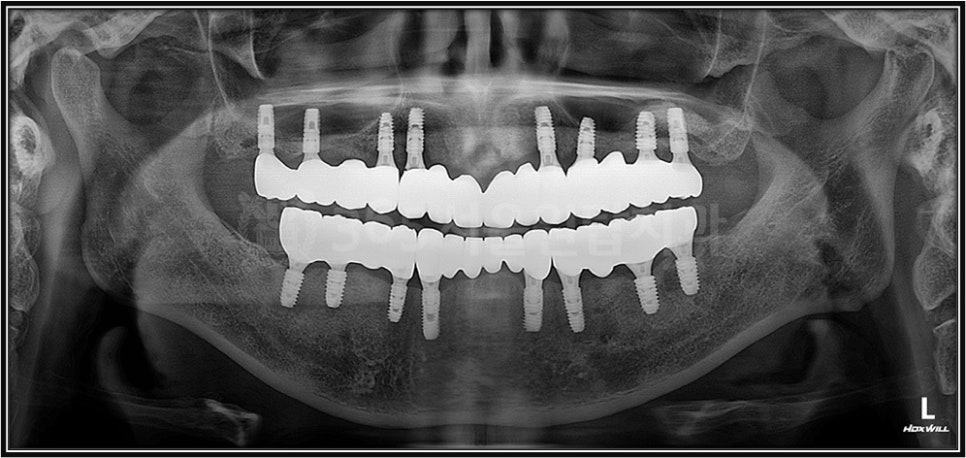

하지만 임플란트 치료에서

제가 가장 신중하게

보는 부분 중 하나는

바로 임플란트 식립 각도입니다.

겉으로는 작은 나사를

심는 치료처럼 보이지만,

1~2도의 미세한 차이가

몇 년 뒤 결과를

달라지게 만들 수 있습니다.

염창역 임플란트의 식립 각도가 중요한 이유는 식립 각도가 틀어질 경우 임플란트에 여러 문제점이 발생될 수 있기 때문입니다